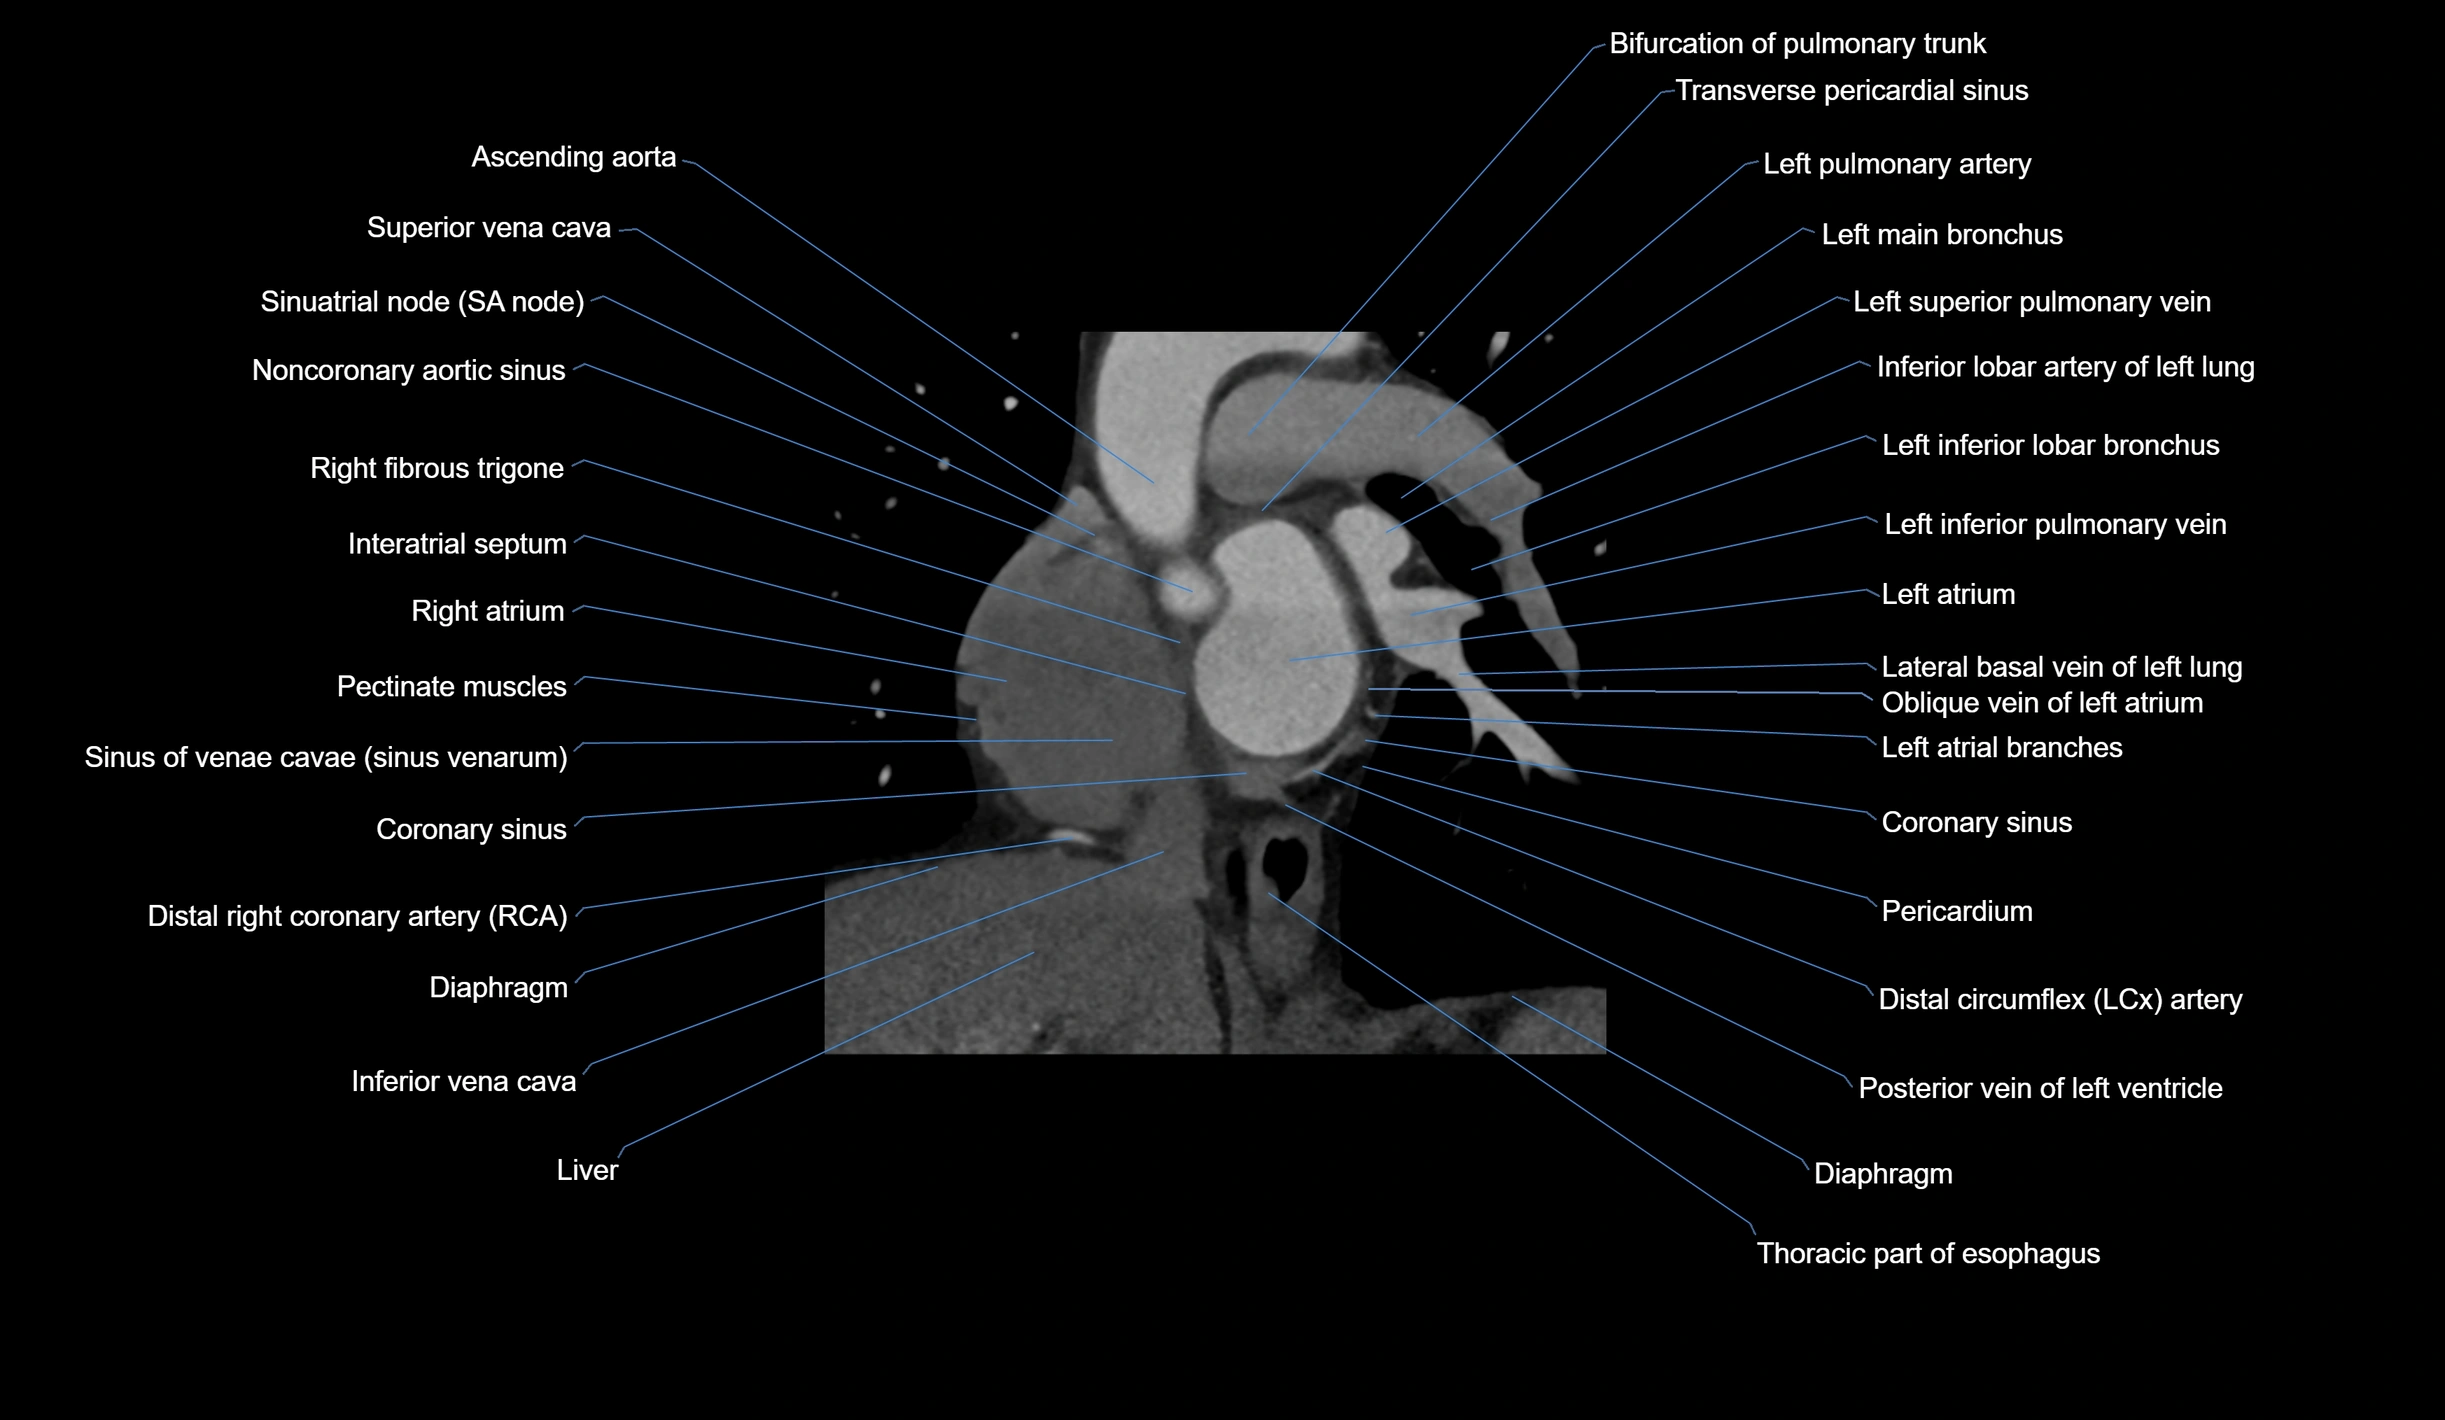

- Ascending aorta

- Coronary sinus

- Coronary sulcus

- Diaphragm

- Inferior vena cava

- Interatrial septum

- Left atrium

- Left inferior pulmonary vein

- Left main bronchus

- Left pulmonary artery

- Left superior pulmonary vein

- Noncoronary aortic sinus

- Oblique vein of left atrium

- Pectinate muscles

- Pericardium

- Posterior vein of left ventricle

- Right fibrous trigone

- Sinoatrial node (SA node)

- Sinus of venae cavae (sinus venarum)

- Superior vena cava

- Transverse pericardial sinus